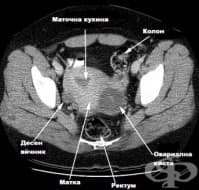

ЯМР на таз

Ядрено магнитния резонанс на таза е нерентгенов метод за послойно изобразяване на органите и структу...